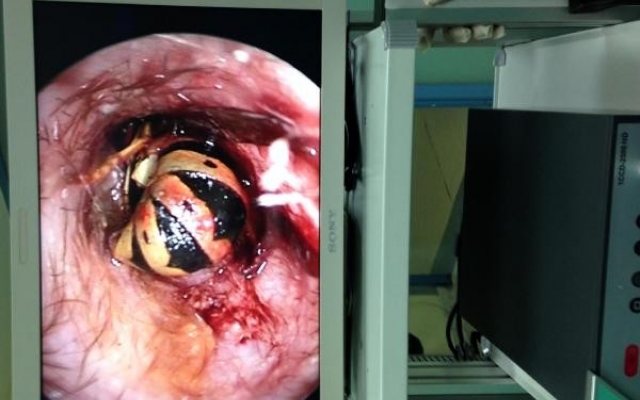

Aynı hastanenin yine KBB polikliniğine kulak ağrısı ve tıkanıklığı ile başvuran 39 yaşındaki Adil Yılmaz'ın kulağında ise arı olduğu görüldü.

Op. Dr. Mustafa Altıntaş, arının sokması nedeniyle hastanın dış kulak yolunun şiştiği ve arının kulak içinde sıkıştığını belirledi. Ameliyathanede endoskopik kamera yöntemiyle bir saate yakın uğraşın ardından kulağındaki arı çıkartılan hasta, bir süre gözlem altında tutulduktan sonra taburcu edildi.